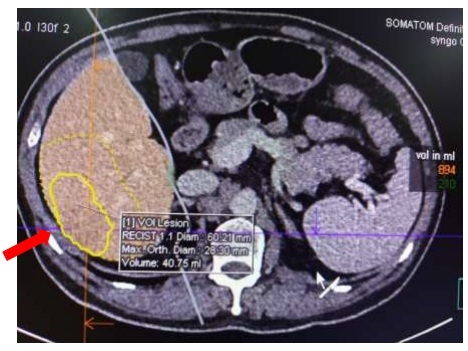

– Chụp MSCT ổ bụng: Hình ảnh u gan hạ phân thuỳ VI, kích thước 2,5×3,5cm, tính chất HCC (ung thư biểu mô tế bào gan). Cạnh khối có vùng ngấm thuốc kém trong cùng hạ phân thuỳ VI. Tĩnh mạch cửa đường kính 15mm, không có huyết khối.

Hình 1: hình ảnh khối u gan hạ phân thuỳ VI, kích thước 2,5×3,5cm, tính chất HCC (mũi tên màu đỏ)

Hình 2. MSCT bụng: Đánh giá khối u (tính chất, số lượng, vị trí), mạch máu nuôi u gan, đánh giá tình trạng xâm lấn mạch máu, di căn ngoài gan, tính thể tích khối u, thể tích các thuỳ gan, toàn gan.

– Thể tích gan trái: 210 ml

– Thể tích gan phải: 894 ml

– Thể tích toàn bộ gan: 1104 ml

– Thể tích khối u: 40,75 ml

– Tỉ lệ u/gan: 0,037